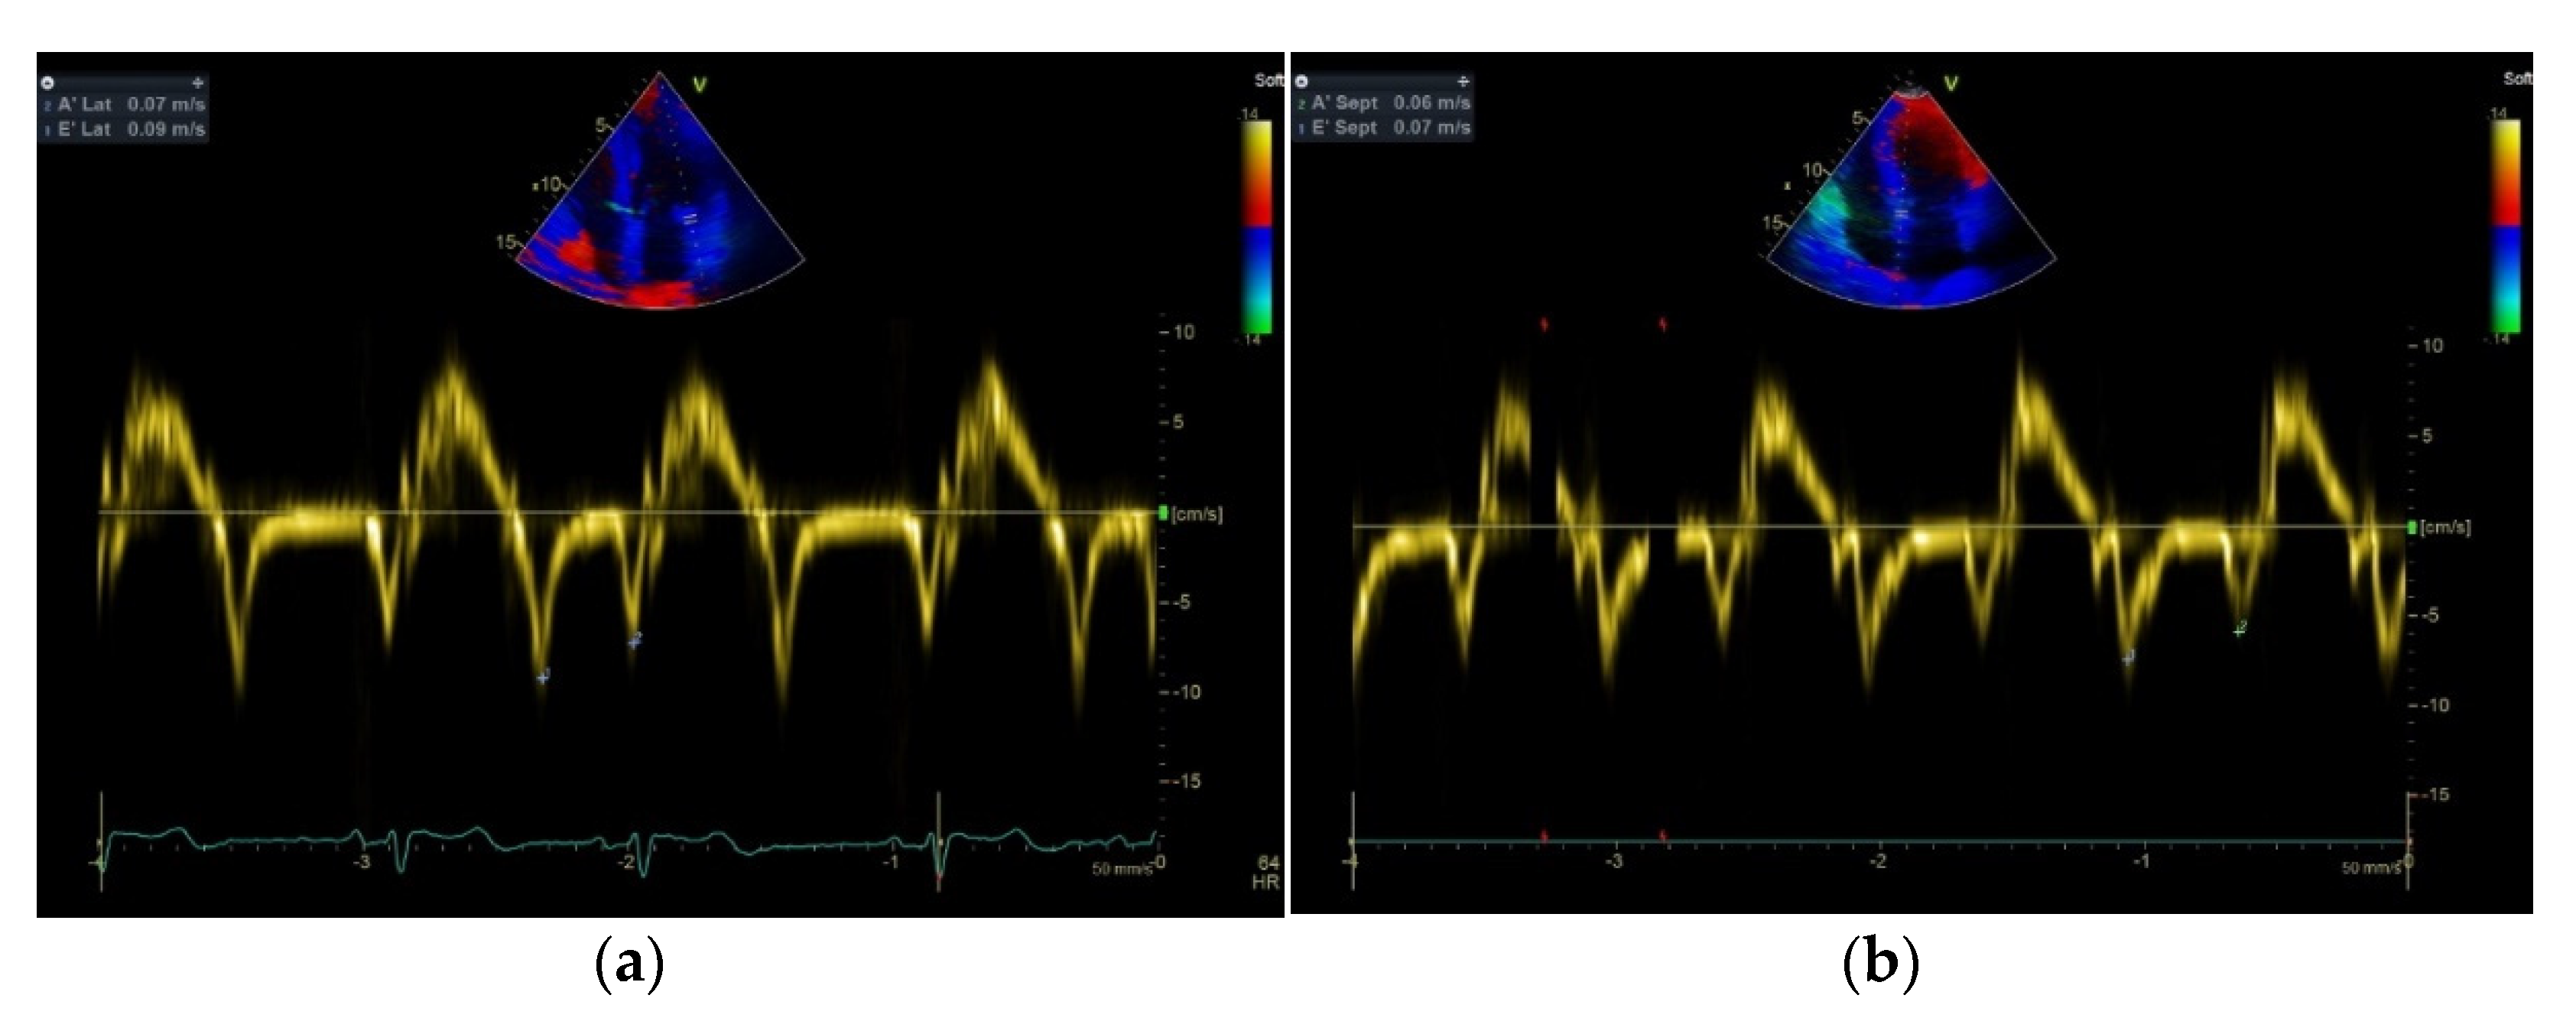

| E/E’ aver | 9.24 ± 1.42 a,b | 7.00 ± 0.9 | 5.76 ± 0.8 |

| Septal E’ velocity (cm/s) | 6.2 ± 0.70 a,b | 10.0 ± 0.9 | 11.1 ± 0.82 |

| Septal A’ velocity (cm/s) | 5.6 ± 0.6 | 6.7 ± 0.6 | 7 ± 0.7 |

| Lateral E’ velocity (cm/s) | 9.1 ± 0.6 a,b | 13.4 ± 0.5 | 14 ± 0.5 |

| Lateral A’ velocity (cm/s) | 7.1 ± 0.5 | 7.9 ± 0.6 c | 8 ± 0.7 |